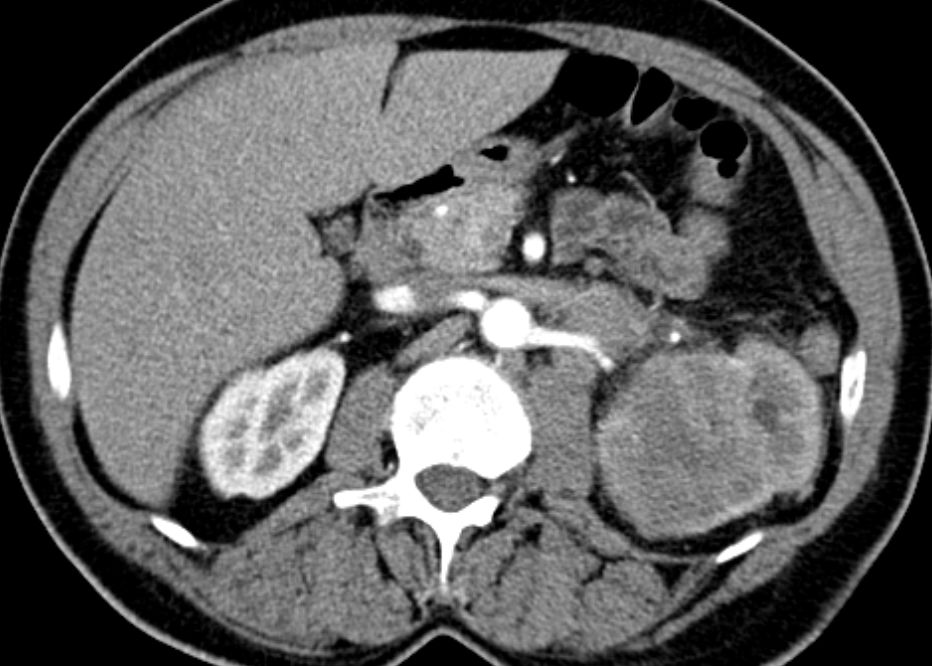

54-jähriger Mann mit

Rückenschmerzen. Bei der Durchuntersuchung wurde eine Metastase in BWK5 mit drohendem Querschnitt gefunden. Es erfolgte eine Laminektomie und Stabilisierung von Pedikelschrauben von T3,4 aud T6,7. Als Primärtumor wurde ein Nierentumor T3 pN2(4/5) m1oss gefunden. |

Histochemie: GATA 3 kräftige Kernfärbung. Zytokeratin 7, Zytokeratin färben Tumorzellen kräftig zytoplasmatisch.Zytokeratin 5/6 negativ. p40 färben einen Teil der Tumorzellkerne. Diagnose: invasives Urothelkarzinom des Nierenbeckens mit Lymphknotenmetastasen. | ||